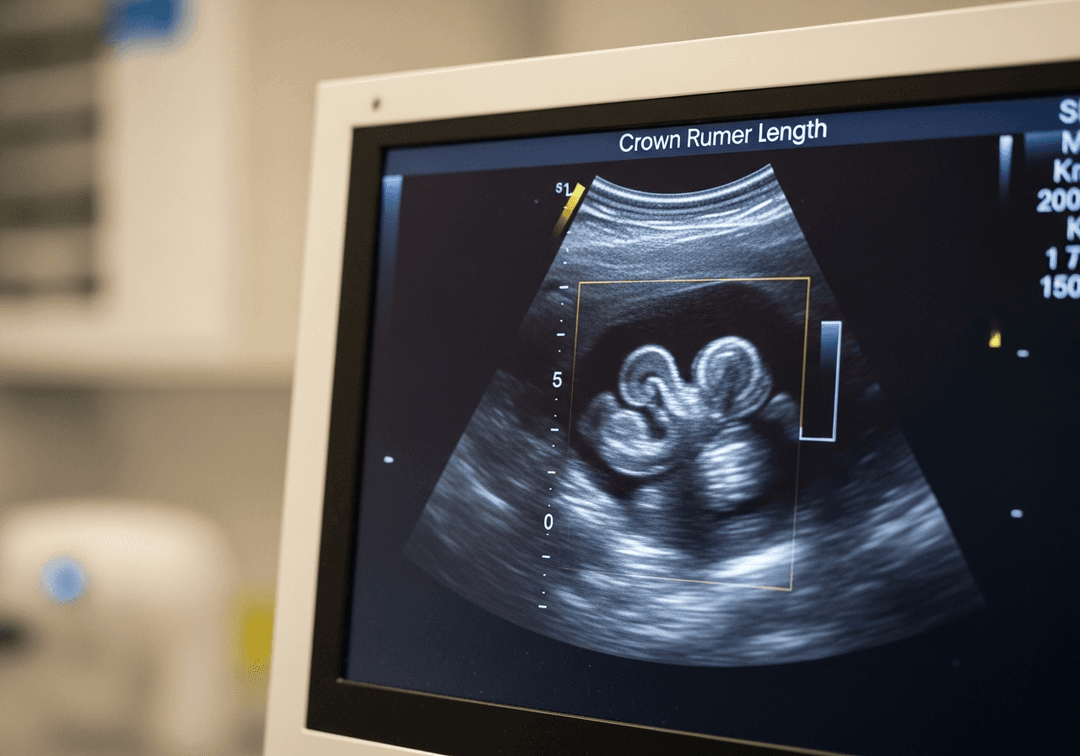

Qu'est-ce que la longueur cranio-caudale ?

La LCC mesure la longueur de l'embryon puis du fœtus, du sommet du crâne (vertex) jusqu'au coccyx (partie inférieure de la colonne vertébrale). Cette mesure exclut les membres inférieurs car ceux-ci sont repliés au premier trimestre.

C'est la mesure la plus précise pour dater une grossesse, avec une marge d'erreur de seulement 3 à 5 jours lorsqu'elle est réalisée dans les conditions optimales.

La LCC est mesurée idéalement entre 7 et 13 semaines d'aménorrhée. C'est dans cette fenêtre que la mesure est la plus fiable pour la datation.